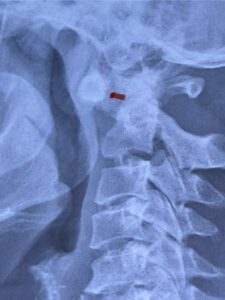

Fig. 5: Lateral cervical x-ray demonstrating widened atlanto-dens interval as a result of instability (red dash).